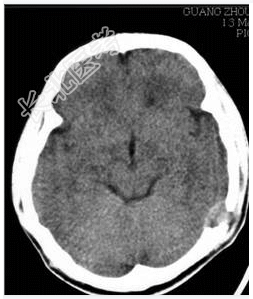

- [材料题] 病历摘要:男性,20岁。

主诉:发现头皮软组织肿物3个月。

现病史:三月前发现左枕部软组织轻微突起伴隐痛,到当地医院检查发现左枕部颅骨骨质缺损,未作具体治疗,现觉头皮肿物增大,时伴有气促、头痛。

专科检查:左颞枕部软组织略膨起,较软,各项病理反射(-)。

- 简答题1、诊断及诊断依据是什么?